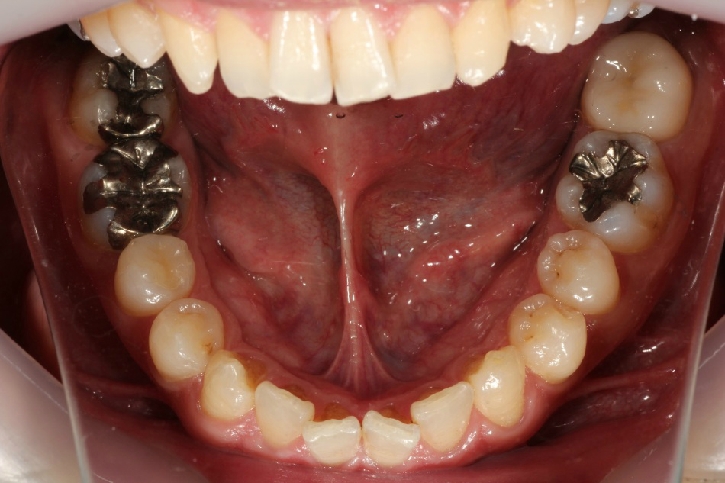

オールセラミックス修復

担当歯科医師:丸林浩太郎

2013年5月11日千葉市中央区 K.N様 上顎12番 オールセラミッククラウン修復